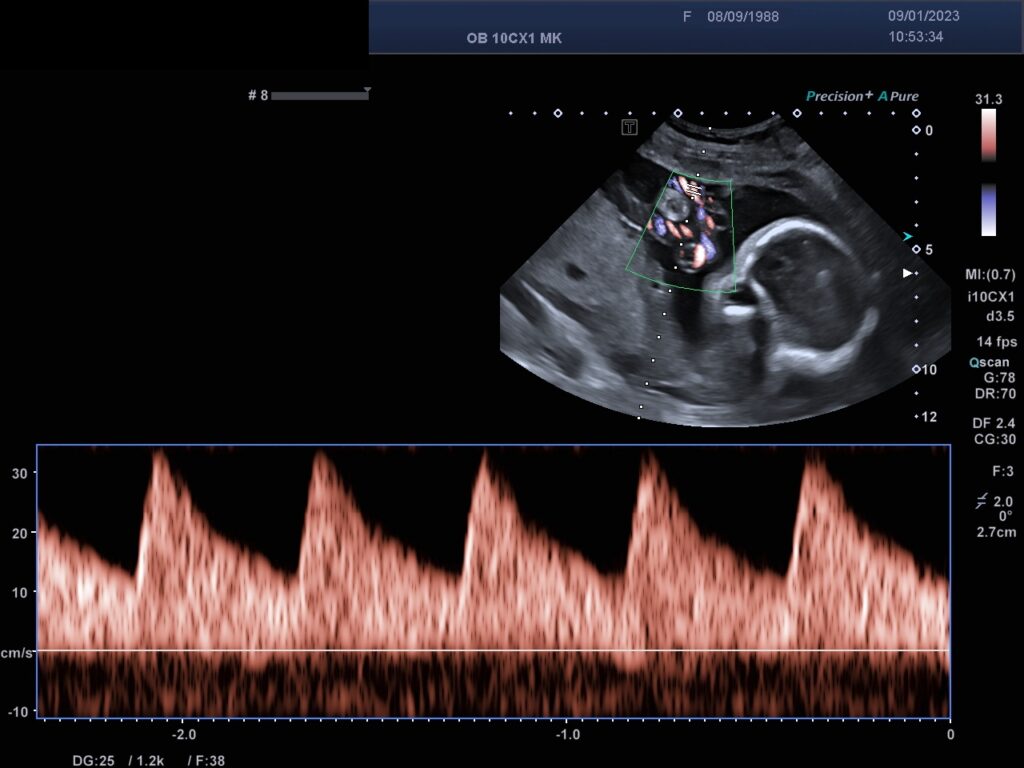

Farb-/ und Spektraldopplersonographie

Mit der Farbdopplersonographie können fetale und mütterliche Gefäße dargestellt werden und dann Spektraldopplerkurven erstellt werden, die semiquantitativ mittels Indices auswertet werden . Damit ist eine Zustandsbeurteilung des Feten als auch der Durchblutungsverhältnisse der Gebärmutterarterien der Schwangeren möglich.

Die Farb-/ und Spektraldopplersonographie ermöglicht die Zustandsbeurteilung des Feten.